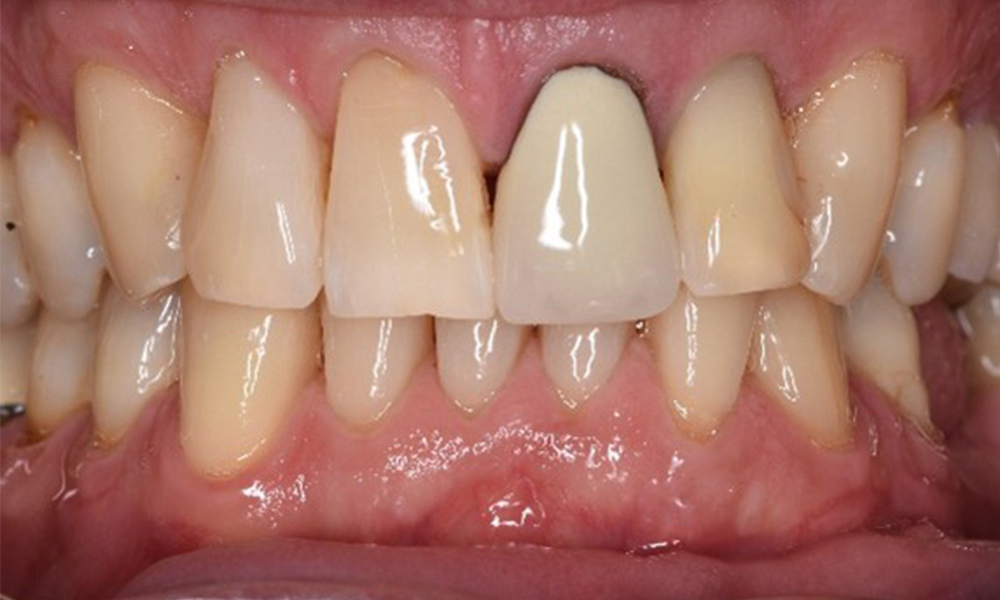

Front view of dentition (upper and lower jaw)

Front view